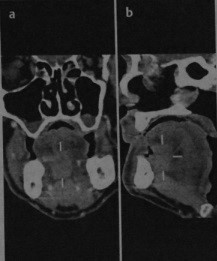

- Неоднородная низкая интенсивность сигнала на Т1-взвешенном изображении

- Незначительное увеличение интенсивности сигнала на Т2- взвешенном изображении

- Точно оценить инфильтрацию мягких тканей и костного мозга можно при исследовании в горизонтальной, фронтальной и сагиттальной плоскостях

- Незначительные артефакты, связанные с зубами

- Усиление после введения гадолиния более четко определяется в последовательности с подавлением сигнала от жировой ткани.

КТ с контрастированием: подъязычный плоскоклеточный рак инфильтрирует мышцы языка, наблюдается гомогенное усиление после введения контраста. Нарушена структура мышечной ткани подбородочно-язычной мышцы. При исследовании во фронтальной плоскости (а) опухоль расположена справа от средней линии над подбородочно-язычной мышцей. При исследовании в сагиттальной плоскости (b) визуализируется опухоль, связанная со слизистой оболочкой и распространяющаяся на собственные мышцы языка (курсор).